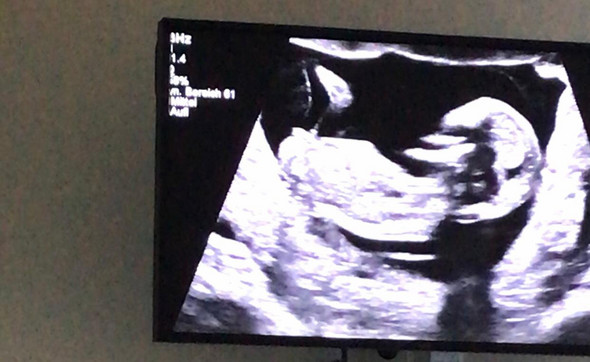

Die ersten 12 Schwangerschaftswochen hast Du hinter Dir, Dein Baby ist jetzt etwa 10 Wochen alt In diesen 10 Wochen ist bereits viel passiert und auf dem Ultraschall sieht man jetzt schon einen richtigen kleinen Menschen Auch in der 13SSW (SSW 1 bis 126) entwickelt sich Dein Baby schnell Womit Du in dieser Woche rechnen kannst, erfährst Du in diesem Artikel. Deine Schwangerschaft ist noch sehr frisch Kommst du jetzt zur Untersuchung ist in der Regel eine hoch aufgebaute Gebärmutterschleimhaut sichtbarDiese entspricht auch der zweiten ZyklushälfteGegen Ende dieser Woche ist in manchen Fällen bereits ein kleiner, schwarzer Punkt zu sehen. Die NackentransparenzMessung (Ultraschall) ist in SSW 13 und 14 möglich Für diesen Zeitraum gelten Grenzwerte für die Dicke der Nackenfalte beim Feten Weichen die Messwerte von den standardisierten Normwerten ab, ist dies ein Hinweis für eventuell bestehende Erkrankungen des Feten.

Für die meisten Mütter gilt in der 13 SSW das Motto "Aufatmen und Geniessen" Die Beschwerden der Frühschwangerschaft sind überwunden, die Belastungen durch das wachsende Baby halten sich in den nächsten Wochen und Monaten noch in Grenzen Ab der 13 Schwangerschaftswoche macht sich die Schwangerschaft jedoch auch äusserlich bemerkbar. Im Ultraschall lässt sich in der 13 SSW das werdende Skelett erkennen Das Baby reagiert auf Geräusche und Berührung Da die Gehörknöchelchen ab der 13 SSW verknöchern, kann das Baby. In der 13 SSW ist der Fötus etwa 6 cm groß Er wiegt circa 18 g Geschafft, das erste Trimester ist vorbei Und für die meisten Frauen beginnt mit der 13 SSW (also 1 bis 126) das angenehmste Drittel der Schwangerschaft das zweite Trimenon Die anfänglichen Beschwerden wie Übelkeit und Kreislaufprobleme sind jetzt meist vorüber.

Wie du deine Schwangerschaftswoche dann ermittelst, erfährst du in unserem Artikel „SSW berechnen“ Was du auf dem 7 SSW Ultraschall siehst Du wirst es kaum glauben, aber bereits in der 7SSW ist auf dem Ultraschallbild, das der Gynäkologe mit seinem Ultraschallgerät zur Verfügung stellt, so einiges zu entdecken. Im Ultraschall lässt sich in der 13 SSW das werdende Skelett erkennen Das Baby reagiert auf Geräusche und Berührung Da die Gehörknöchelchen ab der 13 SSW verknöchern, kann das Baby. Was ist in der 13 SSW auf dem Ultraschall zu erkennen?.